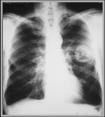

° Lung Cancer